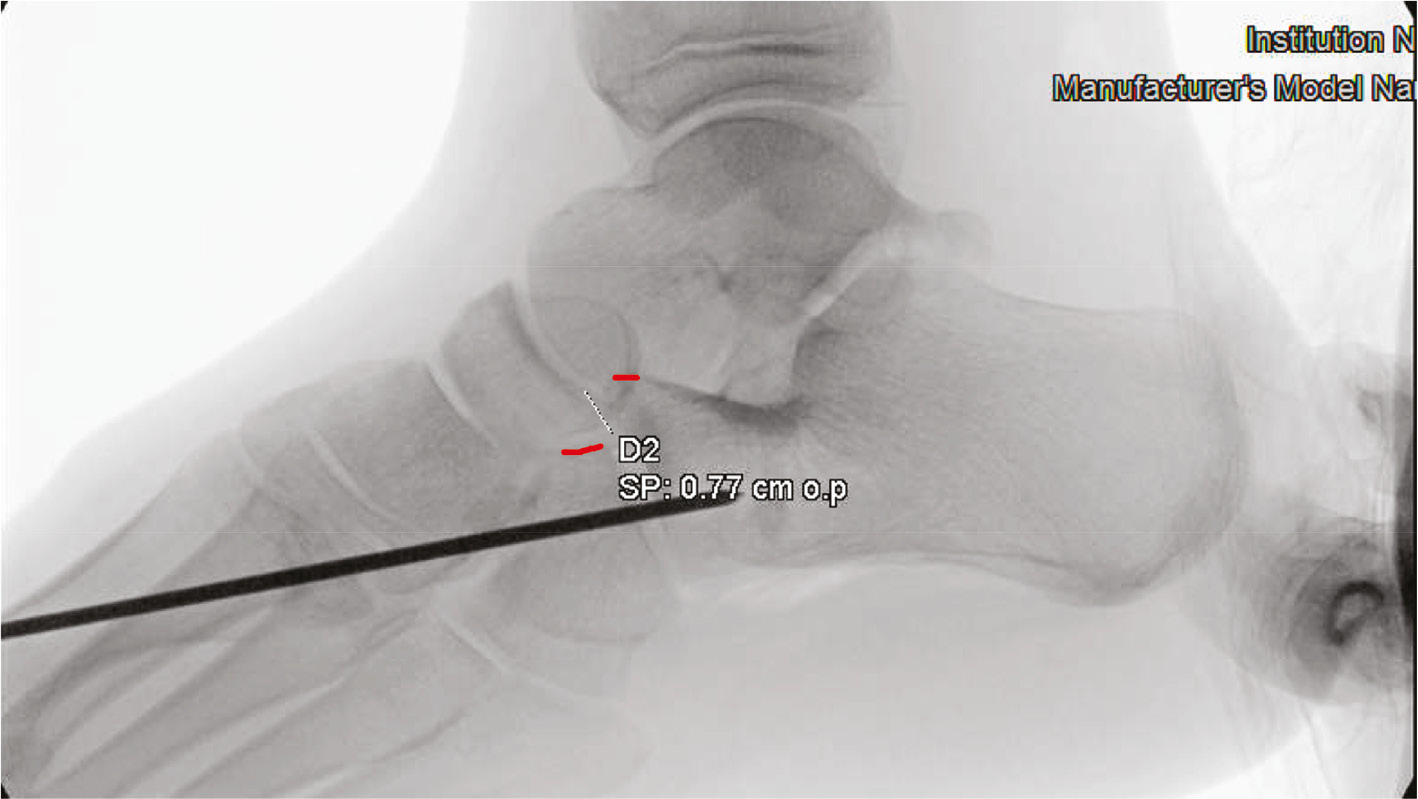

Figure 2. Lateral radiograph after pinning of CC joint and before calcaneal osteotomy. Red lines represent dorsum of calcaneus and cuboid.

jposna2022567_fig2.jpg